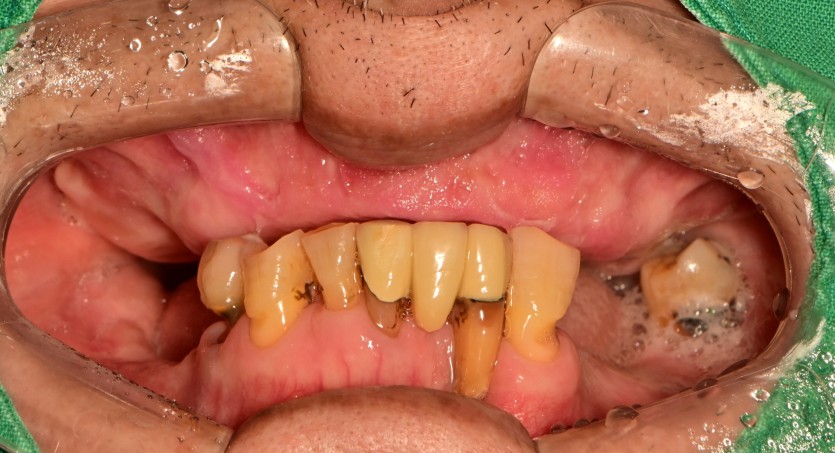

만 73세 전체 임플란트 중례

상, 하악 전체 임플란트 증례입니다.

14개의 임플란트로 완성하였습니다.